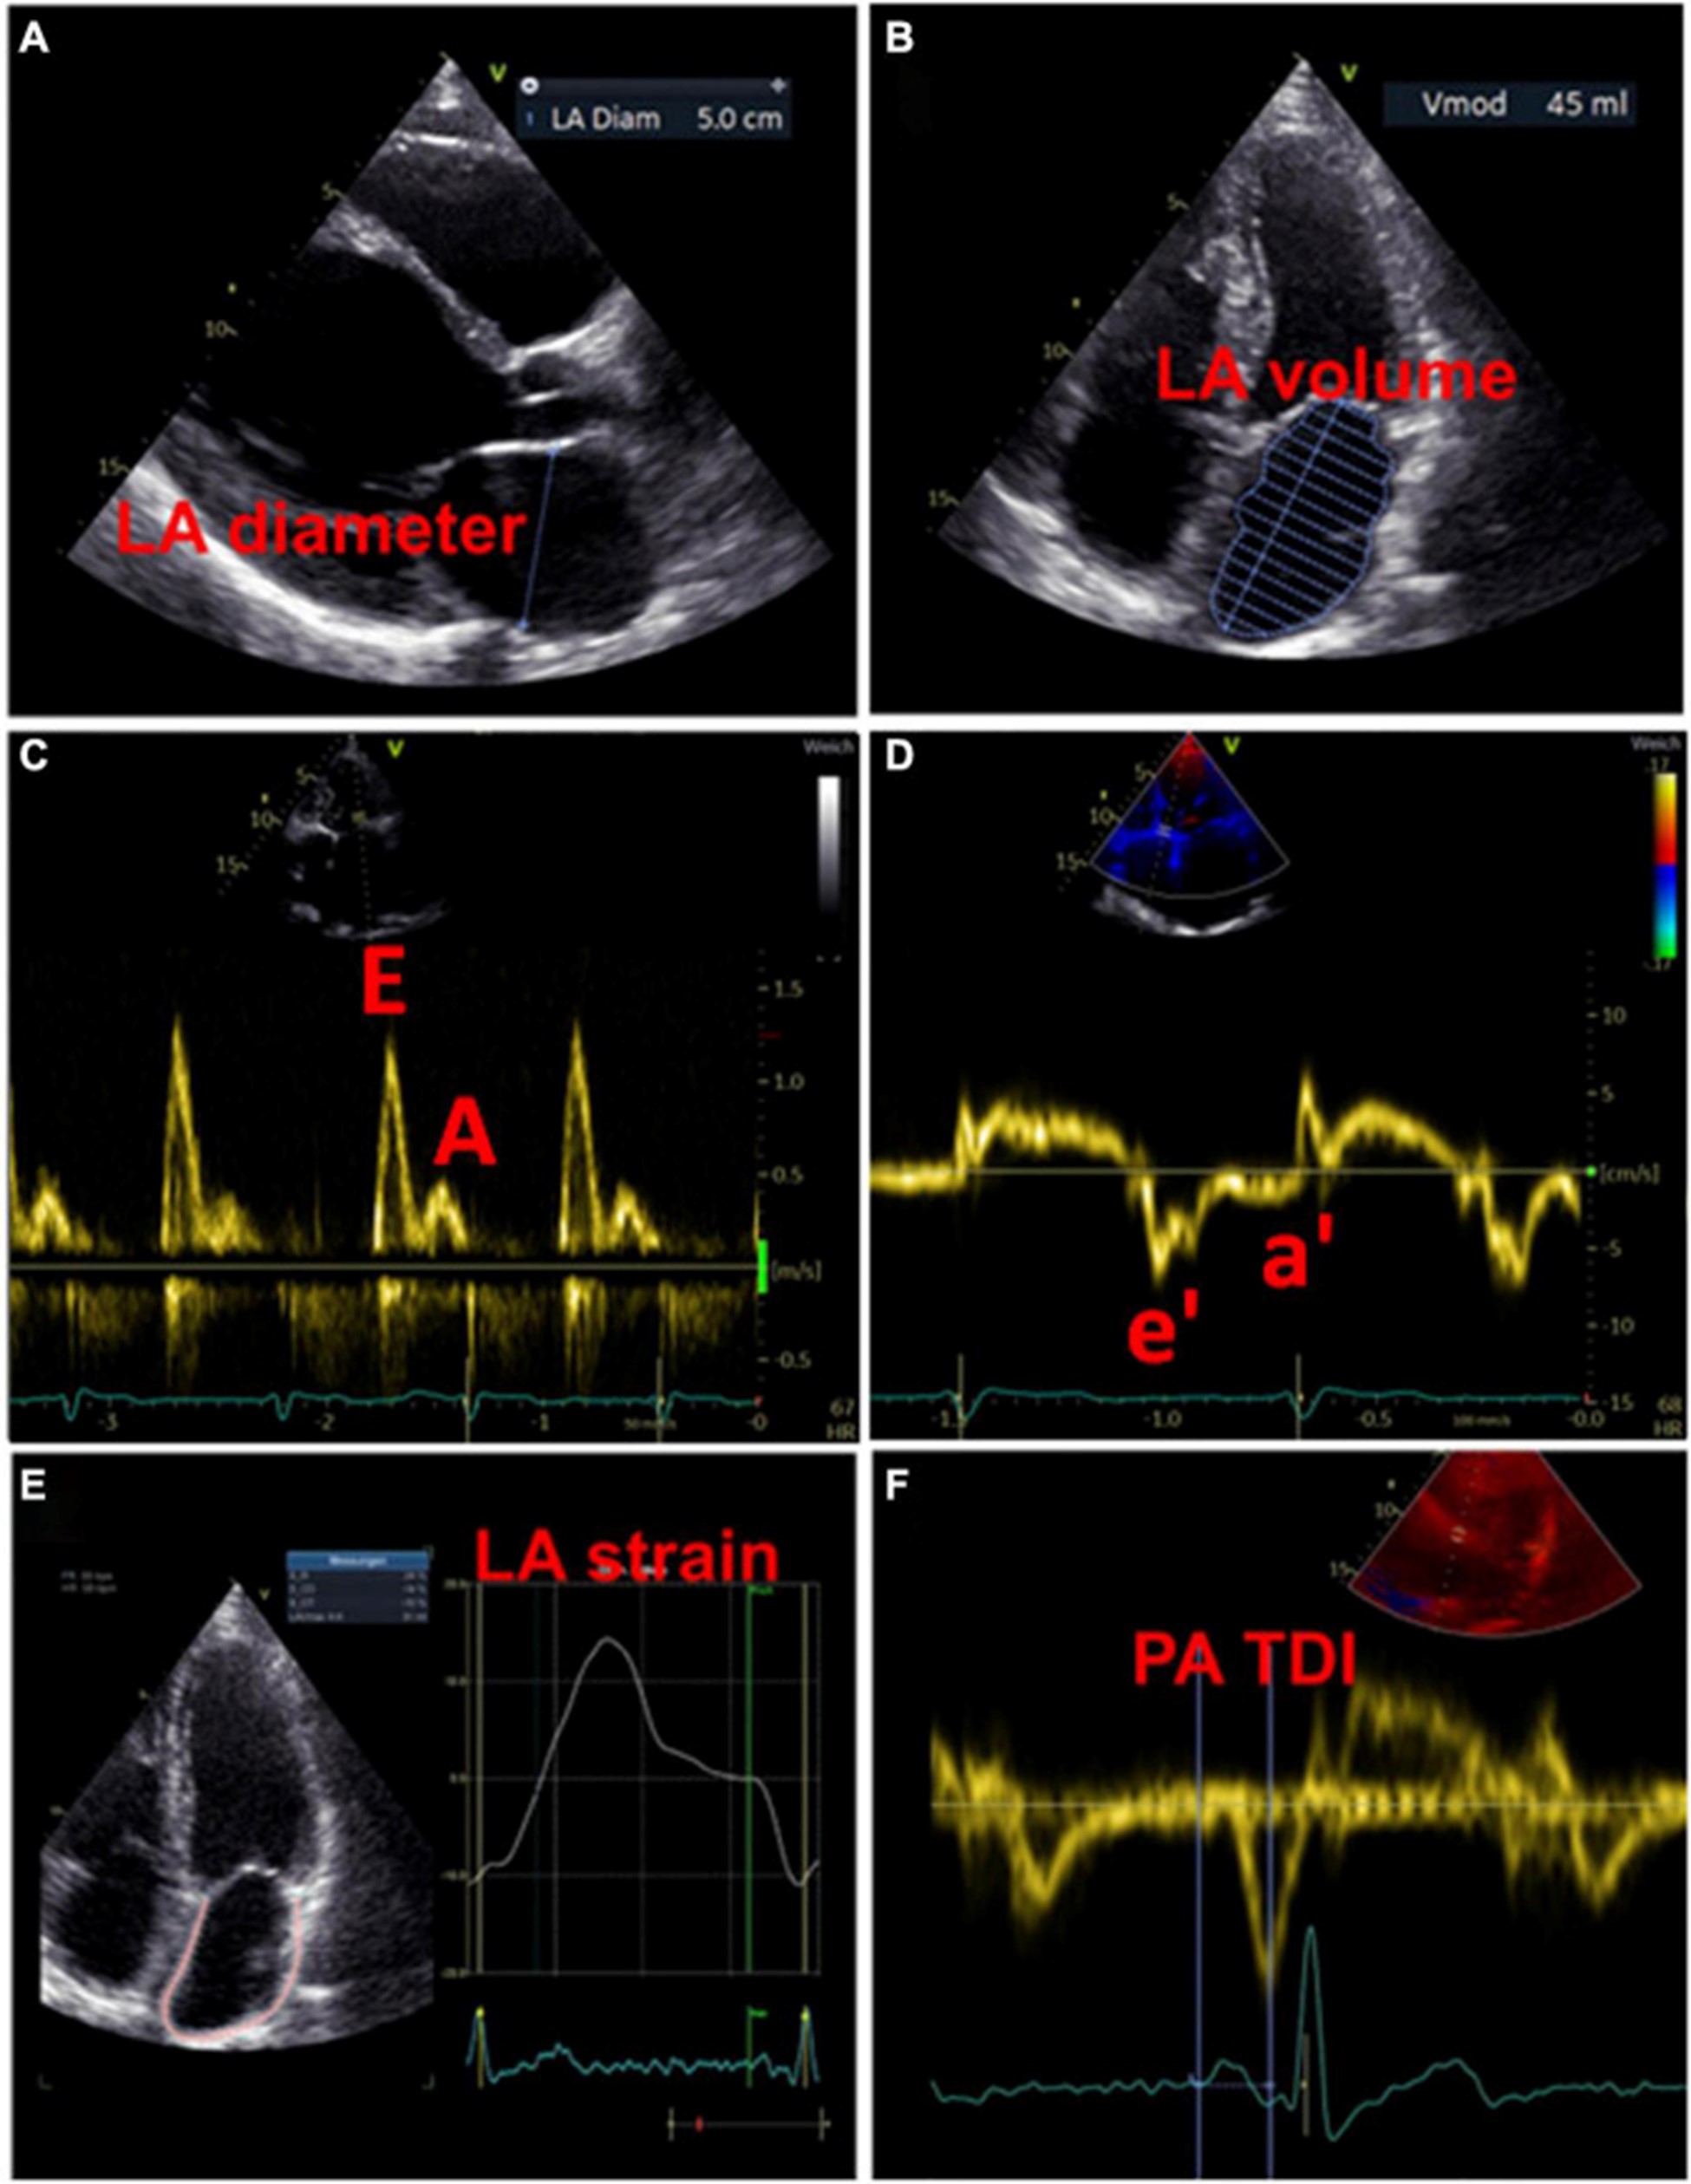

一方面,LA 扩大与心血管不良后果的发生呈正相关是众所周知的 。另一方面,扩大的 LA 也与 AF 的发生有关 。超声心动图是筛查和随访 LA 形态和功能异常患者的首选成像技术,因为它使用广泛、无创且成本效益高 。因此,超声心动图可能有助于检测 LACM。在调查超声心动图效用的研究中,LACM 的定义是证明 LA 大小异常与主要临床结果(如 AF、AF 负担、消融后 AF 复发和缺血性卒中)之间存在关联。表格1)。

左心房大小

用于估计 LA 大小的一个广泛使用的参数是 LA 直径 (图 3A)。在 AFFIRM 研究中,增加的 LA 直径与复发性 AF 相关,但与卒中风险无关 。然而,一项荟萃分析揭示了较大的 LA 直径与中风和血栓栓塞事件的发生率之间存在关联 。此外,大 LA 直径和 LA 体积指数都被证明是主要不良心血管和血栓栓塞事件的预测参数,特别是在没有 AF 的年轻患者中 。LA 容积指数更精确,因此更适合估计心房大小(图 3B)。增加的 LA 体积指数已被描述为心肌功能障碍的潜在早期标志物,并且经常出现在 AF 患者中,在更高的 AF 负担中频率增加 。此外,与似乎没有预测作用的最大 LA 体积相比,最小 LA 体积与新发 AF 和主要不良心血管事件的发生率密切相关 ( 53 – 56 )。

图 3:用于检测左心房心肌病的超声心动图测量示例。(A)测量左心房舒张期的直径。(B)左心房舒张期左心房容积的测量。(C)左心室舒张期的经口流入曲线:第一波代表 E 波(血液被动流入左心室),第二波代表 A 波(左心房主动收缩)。(D)左心室心肌运动的组织多普勒成像,结合(C)心房功能和左心室舒张末期压力的测量结果。(五)左心房的应变分析。(F)测量从 P 波开始(作为心房电活动开始)到 a' 波峰值(心房收缩的机械反应)的 PA-TDI 间隔。

除了代表结构重构的 LA 大小异常外,心房功能评估可能为左心房心肌病的存在提供进一步的重要指标。LA 扩大和 LA 排空分数降低都是 AF 患者的常见现象,LA 大小与排空分数呈负相关 。最近,Eichenlaub 等人。评估了 AF 患者的 LA 排空分数,用于诊断左心房心肌病和预测 PVI 后心律失常复发 。LACM 定义为心内膜接触标测在 0.5 mV 阈值时LA 低电压区域 ≥ 2 cm 2 。LACM 患者的 LA 排空分数低于没有左心房心肌病的患者(27 对 41%,p < 0.0001)(43)。此外,LA 排空分数 < 34% 是 LACM(曲线下面积为 0.846)和 PVI 后心律失常复发的重要预测因素(57)。

多普勒超声心动图

此外,可以通过脉冲波多普勒测量和组织多普勒成像来评估 LA 功能。LA 功能受损可能提示 LACM,在使用多普勒超声心动图的研究中,这与 AF 和 AF 负担等临床结果等同。表格1)。

过去,已经研究了许多与二尖瓣血流和舒张期心肌运动相关的超声心动图参数与 LA 功能和临床事件的关联 。然而,尚未确定适合诊断左心房心肌病的参数和相应的临界值。

虽然 LA 传导功能(以二尖瓣 E 波速度为代表)随着 AF 负荷的增加而增加,但 LA 收缩功能(以二尖瓣 A 波速度和二尖瓣环组织多普勒 a' 速度为代表)具有相反的效果。

。早期 [E] 和晚期 [A] 舒张期充盈波的比率增加与 AF 风险之间存在关联。此外,描述了峰值 A 波速度和 AF 风险之间的 U 形关系 。

二尖瓣环“e”波速度降低和 E/e 比增加表明左室舒张功能受损。有证据表明后一个参数也适用于评估 LA 功能和压力 (图 3C、D)。

通过组织多普勒成像持续时间评估的总心房传导时间

通过组织多普勒成像持续时间评估的总心房传导时间,代表超声心动图得出的总心房传导时间,是结构和电心房重塑的吉祥标志,在窦性心律期间测量为 P 波开始之间的时间间隔在表面心电图上的导联 II 和超声心动图上左室侧壁的组织多普勒成像 (TDI) 跟踪上的 A' 波峰值 (图 3F)。PA-TDI 持续时间延长与节律控制干预后新发 AF、术后 AF 和 AF 复发相关 。在 AF 患者中,血栓栓塞风险的评估通过增加 PA-TDI 持续时间值得到改善。迄今为止,尚未建立 PA-TDI 持续时间的标准参考值。然而,如果每个超声心动图实验室通过常规获取 PA-TDI 值来确定自己的正常值,则可能会改善对 AF 相关结果的风险评估 。

斑点追踪超声心动图

近年来,斑点追踪超声心动图已成为通过评估组织运动来检测早期心肌变形的流行方法 。LA 应变和应变率成像提供了对心房功能重塑的见解。图 3E)。评估斑点追踪超声心动图效用的研究主要通过临床定义(例如,AF、AF 负担、AF 复发、血栓栓塞事件)或通过与电解剖标测中的异常发现进行比较来定义 LACM。表格1)。